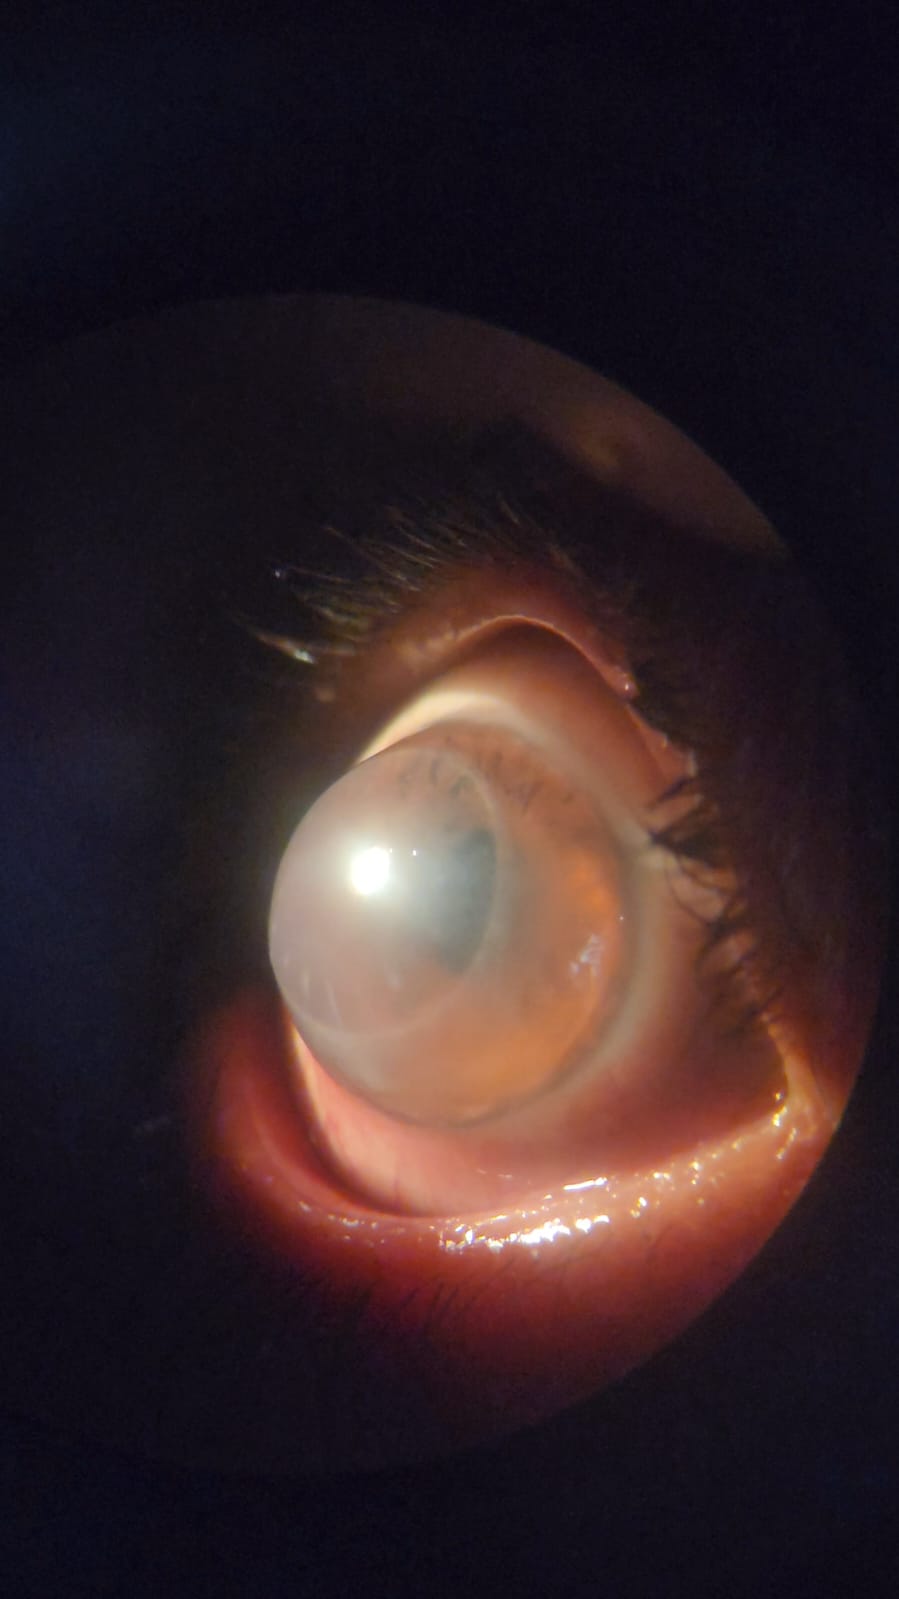

Voici quelques exemples de photos des années passées :